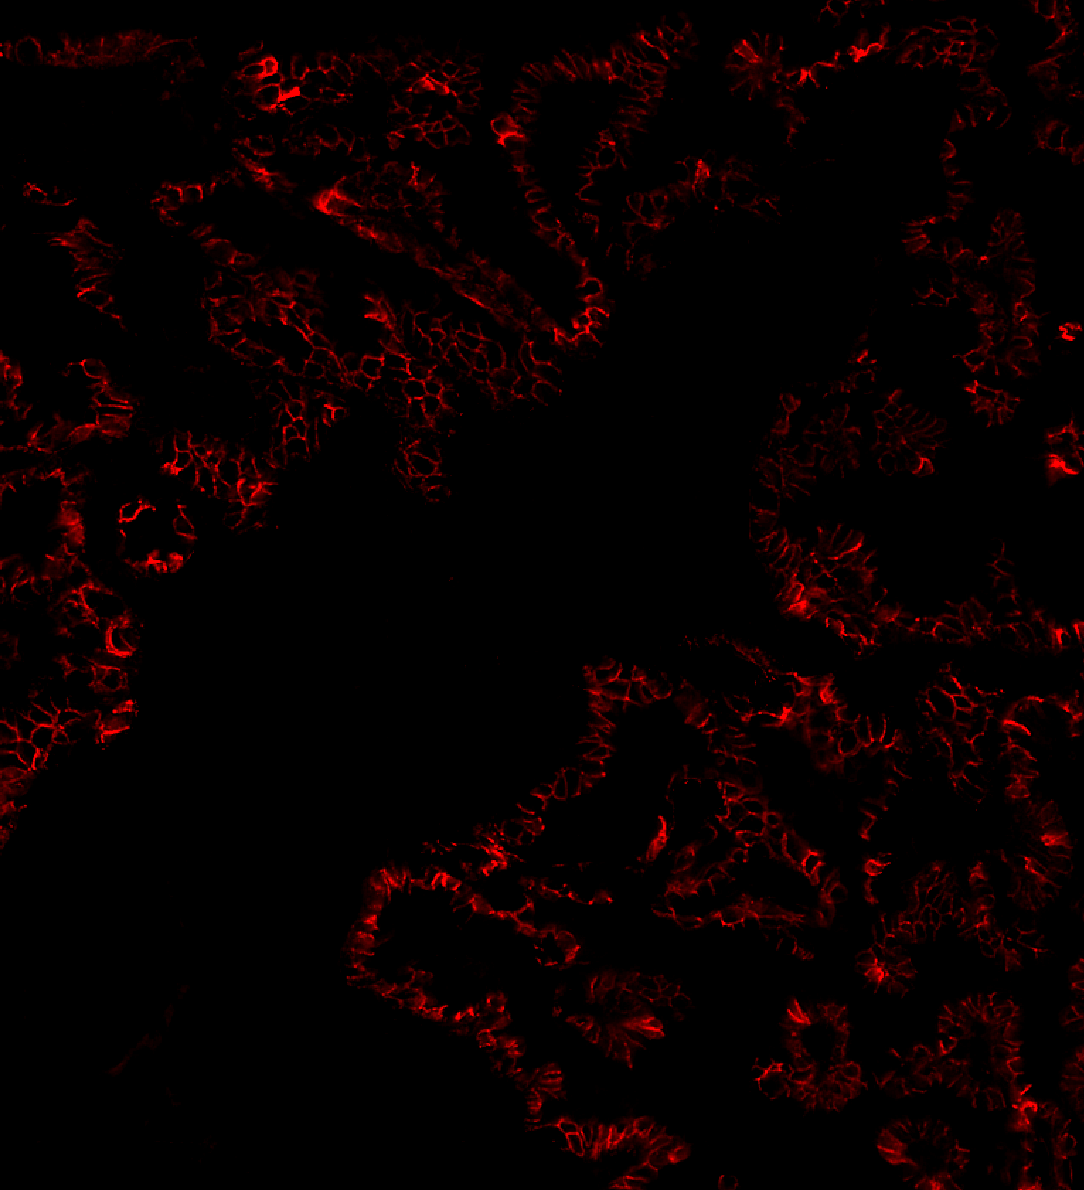

Sarpeda Clear — Background Removal

Lung tissue: E-cadherin signal buried in autofluorescence, then cleaned by AI. The true biological signal emerges with single-pixel detail preserved.

Lung Clear output

Lung input

Input Clear Output

Lung negative control

Negative control — background-only reference used for AI training